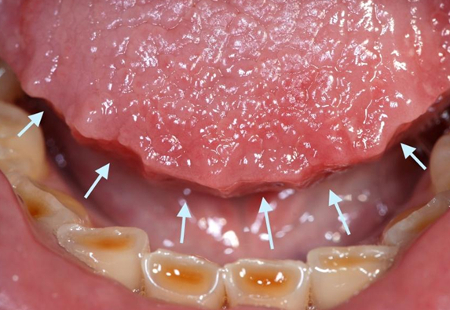

Língua recortada

Da coleção do Dr. Alessandro Bracci